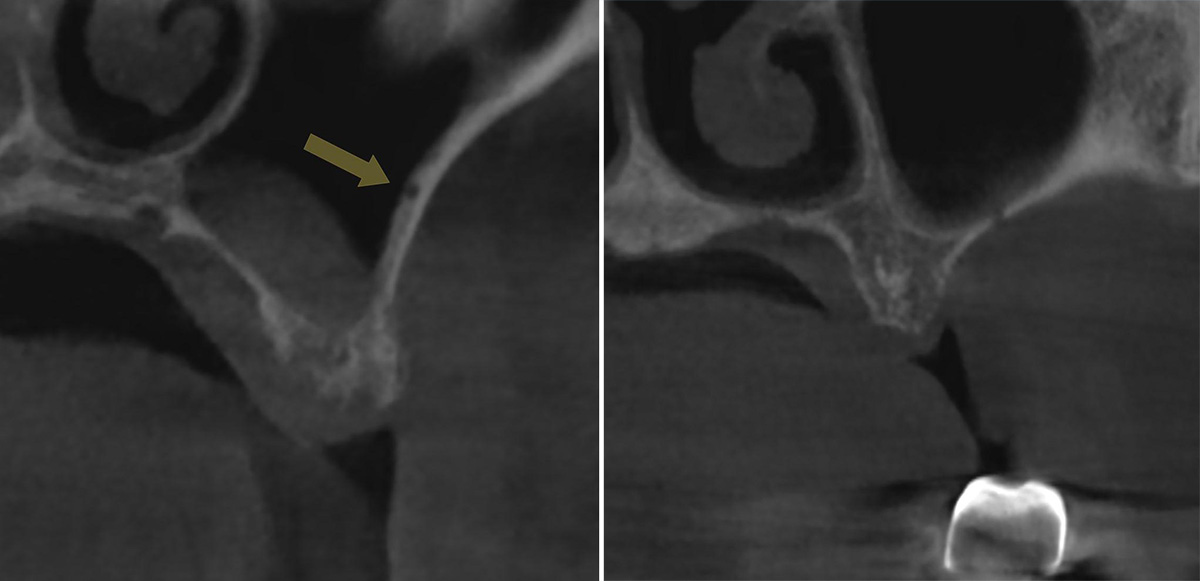

Для определения расположения ААА на КЛКТ важно выявить дискретный канал или вдавление в латеральной стенке верхнечелюстного синуса (рис 1.a, b) [2,16].

Рисунок 1. Рентгенологические признаки альвеоло-антральной артерии на коронарном реформате КЛКТ.

a: вдавление в латеральной стенке верхнечелюстного синуса (стрелка);

b: прерывание стенки верхнечелюстного синуса.